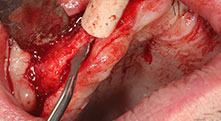

Pourriez-vous décrire brièvement par exemple comment vous procédez pour mobiliser les blocs osseux en vue d’une greffe ?

Pr Bratu : Nous préférons prélever l'os sur la crête oblique externe de la mandibule postérieure, et non dans la région interforaminale. Après l'incision des tissus mous, nous utilisons les nouvelles scies pour définir la quantité d'os à prélever. De la même manière, nous les utilisons également pour la totalité de la préparation dans presque 80 % des cas. Nous avons également parfois recours à d'autres instruments piézoélectriques et, pour terminer, à un burin pour mobiliser le bloc. Nous trouvons cette technique chirurgicale très efficace.

Pr Bratu : Nous avons volontiers recours à la technique sandwich pour les augmentations mandibulaires latérales. La préparation d'un couvercle osseux est réalisée à l'aide de la scie piézoélectrique et le fragment crestal est fixé à l'aide de microvis. Nous plaçons un mélange de matériau de substitution osseuse autologue et xénogénique entre les deux. Cela fonctionne très bien. Il faut toujours s'assurer que les coupes verticales aient des dimensions suffisantes lors du clivage de la crête alvéolaire dans la mandibule. Sinon, l'os risque de se casser facilement.